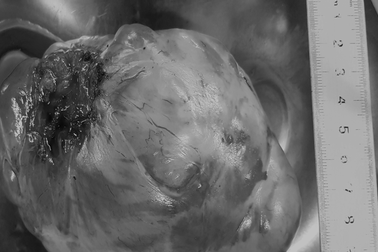

Khó thở, đau ngực vì khối u to như quả cam chèn ép tim phổiChiều 18/9, Bệnh viện ung bướu Đà Nẵng cho biết, vừa phẫu thuật thành công cho một bệnh nhân bị khối u trung thất lớn chèn ép tim, phổi.